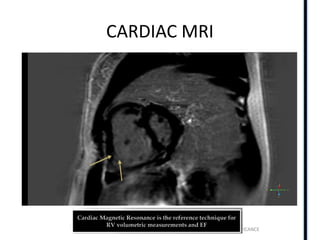

CARDIAC MRI

MR imaging is the imaging modality of

choice in evaluating